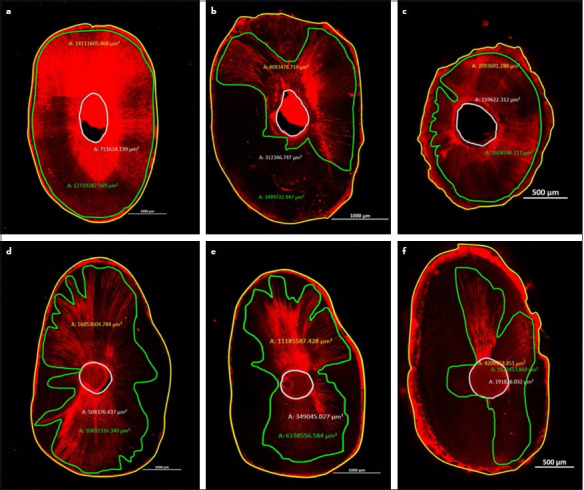

Methods: Eighteen extracted single-rooted mandibular premolars were randomly divided into two groups (n=9) according to the obturation technique used. The maximum penetration depth in microns, percentage of penetration depth, and percentage of penetration area of the NeoSEALER Flo bioceramic sealer were assessed using confocal laser scanning microscopy at different root levels; coronal, middle, and apical. Data was statistically analyzed using Kruskal-Wallis's test followed by Dunn's post hoc test with Bonferroni correction and Friedman's test followed by Nemenyi post hoc test with the significance level set at p<0.05.

Results: The single cone obturation technique has shown a statistically significantly higher percentage area of NeoSEALER Flo penetration than the lateral compaction technique at the coronal root level only. Otherwise, both obturation techniques have shown no statistically significant differences in NeoSEALER Flo penetration distance, percentage of penetration distance, and percentage of area penetration at the middle and apical root levels.